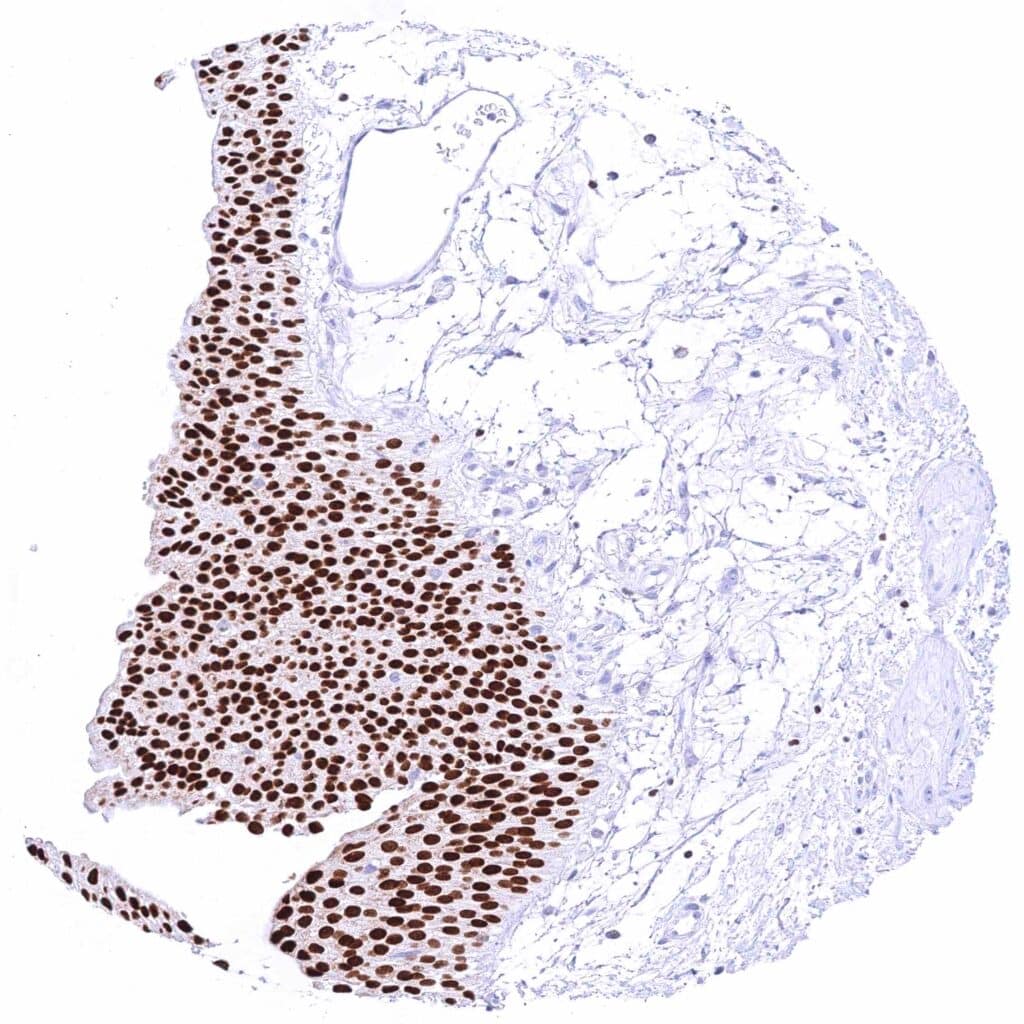

Breast – Moderate to strong GATA3 staining of luminal cells while myoepithelial cells remain GATA3 negative.